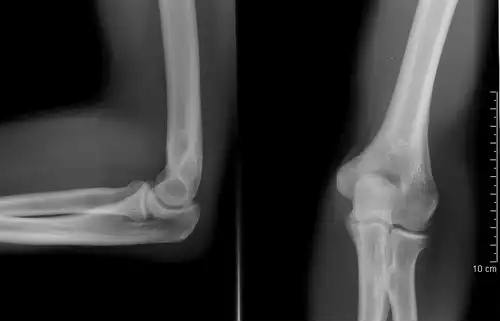

عکس برداری از اعضای بدن و زخم های درونی برای تشخیص بیماری یا شکستگی استخوان یا پیدا کردن محل اشیای خارجی که وارد بدن شده باشد، رادیوگرافی، عکاسی با اشعۀ ایکس.

پَرتونِگاری یا رادیوگرافی ( به فرانسوی: Radiographie ) شیوه بررسی بدن با تاباندن پرتوهای ایکس بر آن و تولید تصویرهایی بر روی کلیشه یا پرده های حساس را گویند.

پرتونگارها یا رادیوگراف ها که به آن ها «رونتگنوگراف» هم می گویند، و پس از کشف پرتوهای ایکس ( اشعه ایکس )، توسط «ویلهلم رونتگن» مشهور شدند، توسط انتقال اشعه ایکس از میان بدن بیمار به یک دستگاه ضبط کننده و سپس تبدیل آن به یک تصویر برای تشخیص، پدید می آیند. در اصل و در حال حاضر هنوز هم به طور معمول، تصویرها بر فیلم های آغشته به نقره یا اشباع شده با آن ثبت می شوند. در رادیوگرافی نوع «فیلم. اسکرین» ( فیلم - - صفحه ) یک لامپ اشعه ایکس، تولید یک بیم یا پرتو از اشعه ایکس می کند که بیمار با آن هدف قرار داده می شود. پرتوهای ایکس از طریق بدن بیمار عبور کرده و به منظور کاهش پراکندگی و صدای اضافی ( نویز ) از آنها، فیلتره می شوند و سپس بر روی فیلمی به صورت نامرئی ظاهر می شوند، که با یک صفحه از نور ساطع شده از فسفرهایی که در کاست ال. تی light - tight cassette نگه داشته می شود، برخورد می کنند. سپس فیلم به صورت شیمیایی ظاهر می شود و یک تصویر بر روی فیلم به نظر می رسد. در حال حاضر رادیوگرافی دیجیتالی یا DR جایگزین رادیوگرافی فیلم - اسکرین شده است. در دیجیتال رادیوگرافی، اشعهٔ ایکس به یک سطح از حسگرها ( سنسورها ) برخورد می کند که بعد از تبدیل به سیگنال هایی که تولیدکننده اطلاعات دیجیتال هستند به یک تصویر در روی صفحه نمایش کامپیوتر تبدیل می شود. رادیوگرافی ساده تنها تصویر با کیفیت در دسترس، در طول ۵۰ سال اول استفاده از رادیولوژی بوده و هنوز هم به علت دسترسی وسیع، و سرعت و هزینه نسبتاً پایین آن، اولین مطالعه دستور داده شده ( تجویز شده ) در ارزیابی از ریه ها، قلب و اسکلت است.

رشته ای علمی برای تولید تصویر روی فیلم عکاسی یا صفحۀ فلوئورسان، با استفاده از تابش، به ویژه با پرتو ایکس. پرتو ایکس، بسته به ماهیت، چگالی و ضخامت ماده، در آن نفوذ می کند و در نتیجه، سایه ای از ماده روی فیلم عکاسی می اندازد. حاصل این عمل رادیوگراف است. در پزشکی، برای بررسی استخوان ها و بافت ها؛ و در صنعت، برای بررسی مواد جامد به فراوانی از پرتونگاری استفاده می کنند. بازرسی درزهای جوشکاری شده در خطوط لوله از آن جمله است.